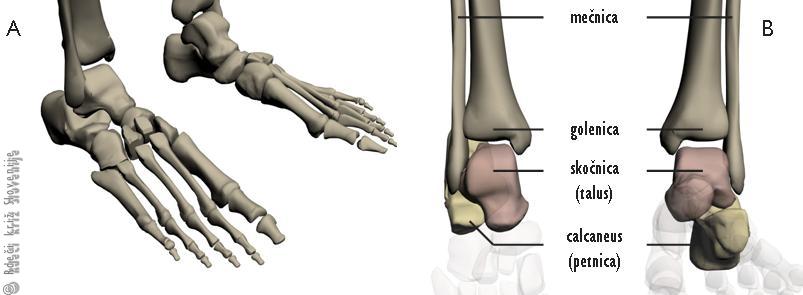

Slika 7

A – Kosti stopala.

B – Zgornji skočni sklep v nevtralnem položaju in plantarni fleksiji (levo).